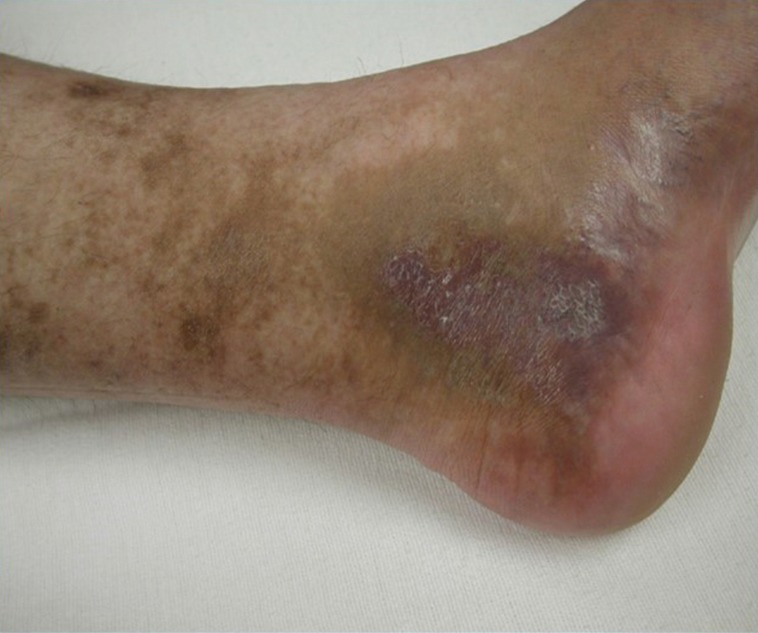

Figure 2.

The clinical example of venous ulceration and hyperpigmentation that can occur in patients with MTS. MTS, May-Thurner syndrome.